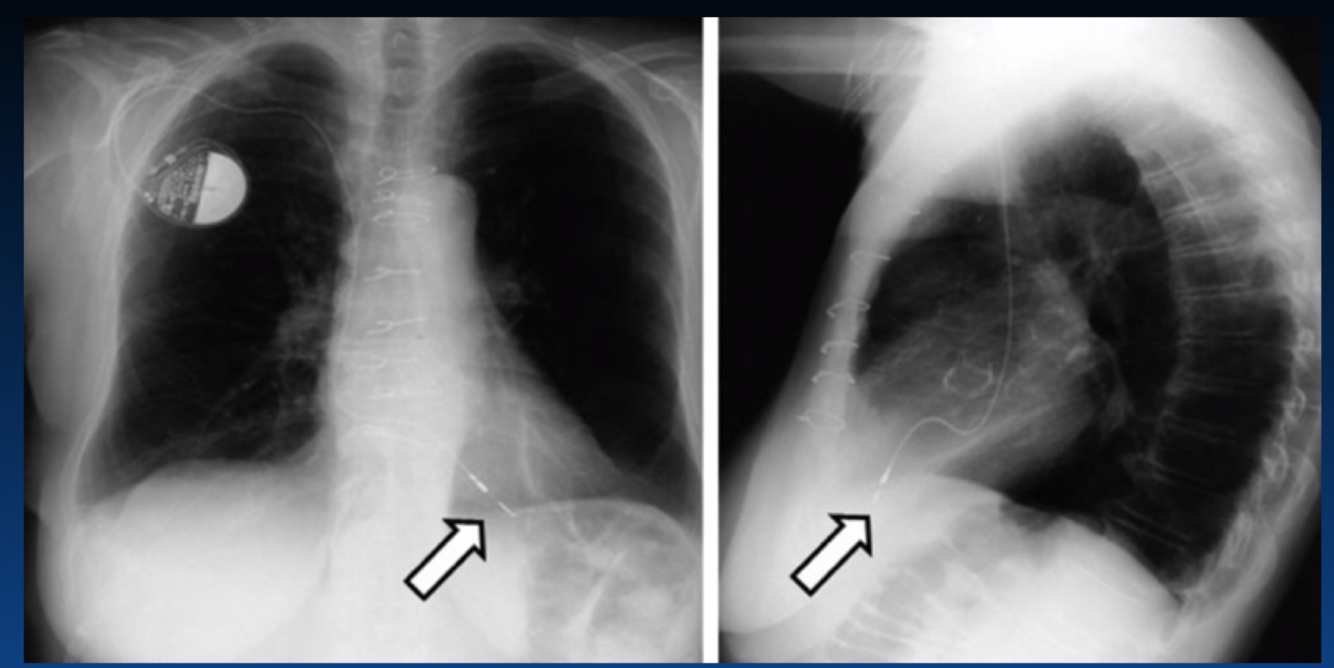

What is shown at the arrow?

What condition caused this? (the white arrow?)